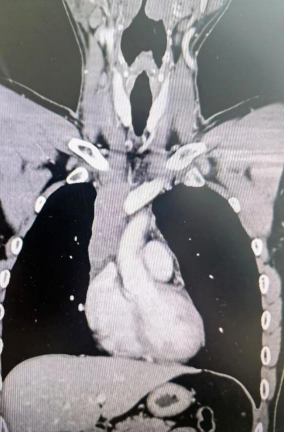

經(jīng)檢查發(fā)現(xiàn)患者前上縱隔腫瘤已經(jīng)完全侵犯了我們?nèi)梭w最主要的大靜脈之一——上腔靜脈,導(dǎo)致上腔靜脈回流嚴(yán)重受阻并導(dǎo)致由上腔靜脈起至左側(cè)無名靜脈、右側(cè)鎖骨下靜脈、右側(cè)頸內(nèi)靜脈等多根自上往下回流的靜脈阻塞,從而形成了廣泛的栓子,牢牢堵住了要流回心臟的血流,只能靠別的一些側(cè)支循環(huán)超負荷的工作,這也就是為什么孫先生脖子甚至是頭都明顯腫起來的原因。

4月30日,麻醉完成后,縱劈胸骨顯露右上縱隔腫瘤,發(fā)現(xiàn)腫瘤侵入上腔靜脈起始部,右鎖骨下靜脈及右頸內(nèi)靜脈血栓形成并向遠端延伸。劉志主任團隊將切口向右頸部延長,顯露右側(cè)頸內(nèi)靜脈至下頜角水平。張金洲副院長團隊經(jīng)股動靜脈和左無名靜脈建立體外循環(huán)。在阻斷左無名靜脈遠端后,李文海副院長團隊完整切除縱隔腫瘤及部分上腔靜脈、左無名靜脈、右鎖骨下靜脈和右頸內(nèi)靜脈切除。張金洲副院長團隊實施了無名靜脈近端、右鎖骨下靜脈和右頸內(nèi)靜脈內(nèi)血栓取出術(shù),并完成了左無名靜脈、右頸內(nèi)靜脈和右鎖骨下靜脈的人工血管置換手術(shù)。歷時6小時,三個外科團隊在麻醉科柴偉主任團隊、體外循環(huán)團隊以及食管超聲和手術(shù)室協(xié)作下,手術(shù)獲得成功。

術(shù)后患者經(jīng)過心外監(jiān)護室和胸外監(jiān)護室的接力治療,目前患者恢復(fù)順利,顏面部腫消失。復(fù)查增強CT三條人工血管通暢。